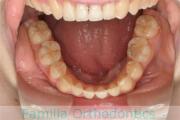

No.22V-133

- 下顎前突

- 叢生

- 41歳

- 男性

- 抜歯部位

- 下:

- 88

- 主な使用装置:

- FEA 022

- 治療にかかった費用:

- 保険

受け口を治したいということで来院されました。下の親知らずのみ抜歯してマルチブラケット法を行いました。術前矯正治療が終了後、入院・手術を行っています。約3年、35回程度の通院が必要でした。

外科的矯正治療には、矯正治療単独で行った場合のリスクや副作用に加えて、外科手術のもつリスクがあります。

全身麻酔や入院の必要性、術後の疼痛や顔の腫れ、手術部位周囲の感覚麻痺などがそれにあたります。

- ≫治療前

上顎

下顎

- ≫治療後